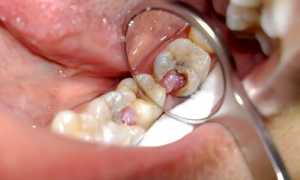

Чувствительность: ощущение, что они чешутся, разъедутся

Если после удаления восьмёрки, остальные зубы стали чувствительны к высоким и низким температурам, появилось ощущение зуда, это может быть симптомом неврологической патологии или воспаления дёсен и костной ткани.

Фото 1. Воспаление десен – причиной может стать распространение бактерий от больных зубов во время операции.

В первом случае, во время операции по удаления зуба, врач мог случайно повредить нервное окончание или оставить в ранке осколок зуба. Если это произошло, рекомендуется повторно обратиться в больницу, для обнаружения точной причины неприятного последствия. Для устранения проблемы придётся прибегнуть к оперативному вмешательству.

Если причиной зуда и чувствительности стало воспаление слизистой, значит рядом с опустевшей лункой находится зуб, поражённый кариесом. Во время операции по удалению восьмёрки врач обязательно санирует полость рта, но это не даёт гарантии того, что болезнетворные бактерии не попадут в ранку.